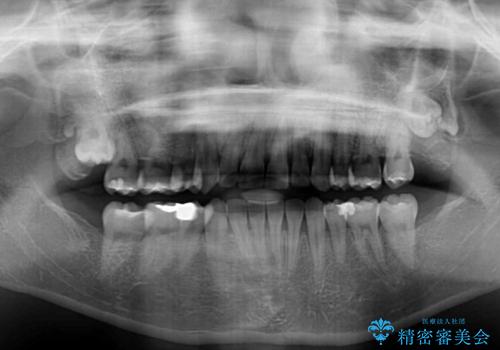

当初予定は2年半程度と伝えていましたが、2年にも満たない期間で治療を終えることができました。